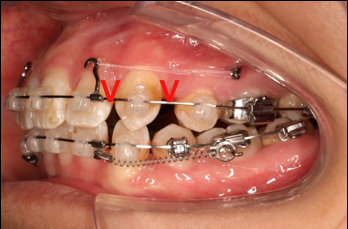

4.第6个月:2017.04.28 ◆ 上0.016*25ss 13/23v形曲,下0.017*25ss

2017.04.28

2017.04.28  上0.016*25ss 13、23近远中约5度 v形曲,下0.017*25ss

上颌矫治的生物力学

上颌使用高位种植钉及长牵引钩,配合尖牙近远中的v-bend,上颌前牙的牙齿移动方式是整体往上,往后内收。